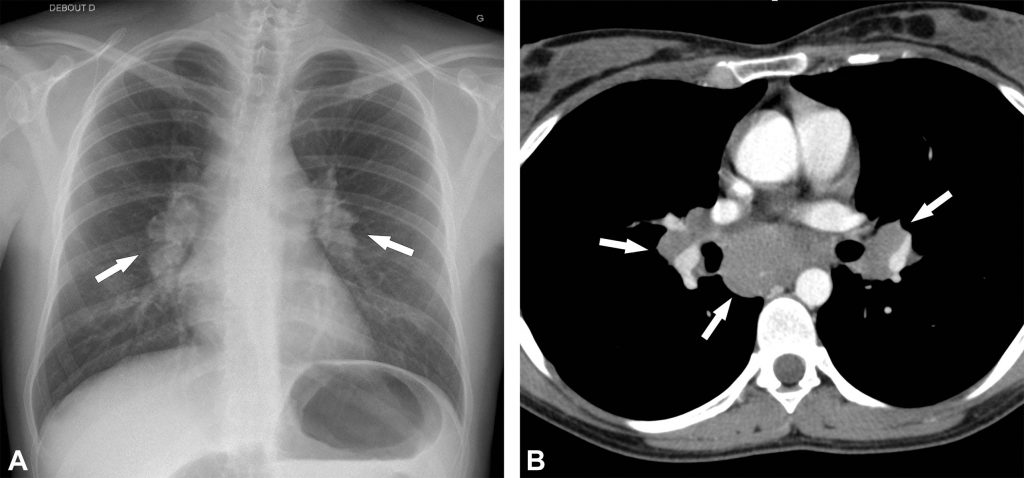

- stade 1 : adénopathies hilaires ou médiastinales bilatérales (figure 99.2) ;

Fig. 99.2. Sarcoïdose de stade 1.

La radiographie thoracique de face montre une hypertrophie des hiles pulmonaires liée à des adénopathies (flèches en A) et pas d’anomalie parenchymateuse. Cet aspect est celui d’une sarcoïdose stade 1. Le scanner thoracique injecté réalisé chez le même patient montre l’hypertrophie ganglionnaire médiastino-hilaire bilatérale et symétrique (flèches en B).

Source : CERF, CNEBMN, 2022.